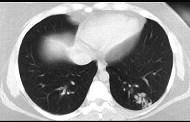

问题 30岁,偶有干咳,结合影像图像,选择最可能的诊断 ( )

选项 A.左下肺感染 B.左下肺结核 C.左下肺错构瘤 D.左下肺炎性假瘤 E.左下肺动静脉畸形

答案 E